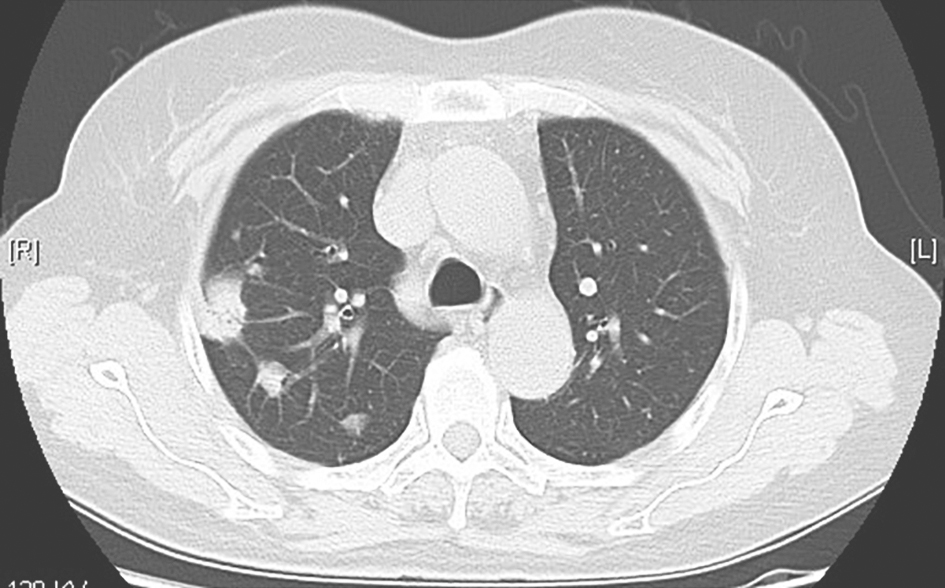

临床确诊后,给予3HRZE/9HRE抗结核治疗,1年后复查胸部CT,示双肺原结节样病灶明显吸收(图8)。

图8 抗结核治疗1年后胸部CT表现